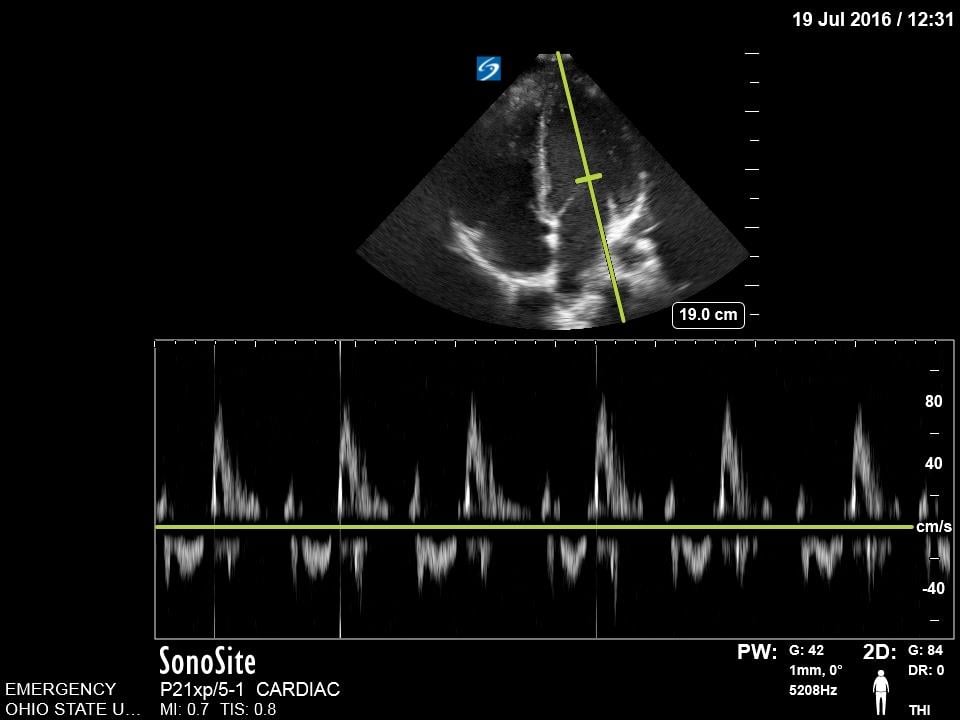

Mitral Valve Inflow

The mitral valve inflow is obtained by placing the pulse wave doppler gate at the tip of mitral leaflets in the apical four chamber view. In cases of suspected cardiac tamponade, a respiratory variability of greater than 25% is concerning for an exaggerated variation due to tamponade physiology.18 Although more advanced, this measurement can also be used for diastology.

Figure 14. Normal Mitral valve inflow on pulse wave doppler